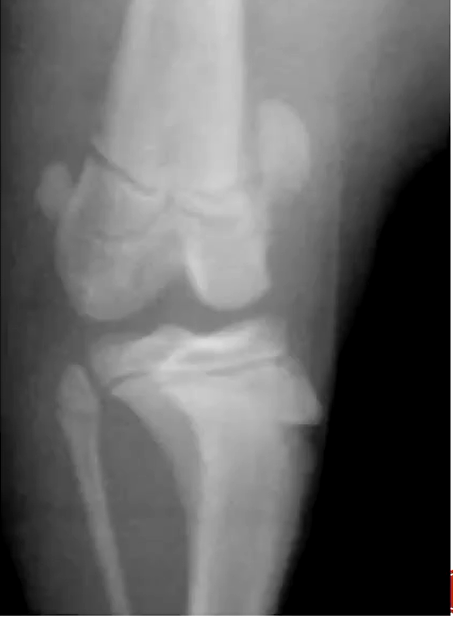

What are the radiographic findings of osteochondrosis in the stife?

Flattening or subchondral defect

Subchondral sclerosis

Detached mineralized cartilage flap

DJD

Osteochondrosis